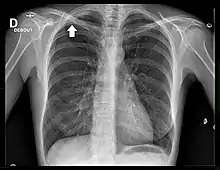

La radiographie thoracique est un examen de dépistage aisément accessible. Cependant, les tumeurs de l'apex de petite taille sont difficiles à visualiser en raison des superpositions osseuses de la clavicule et de la première côte[18].

Le cliché thoracique de face retrouve le plus souvent un simple épaississement de l'apex thoracique, ou bien une authentique masse pulmonaire englobant l'apex[20]. Une ostéolyse des côtes et du rachis est parfois visible[20].